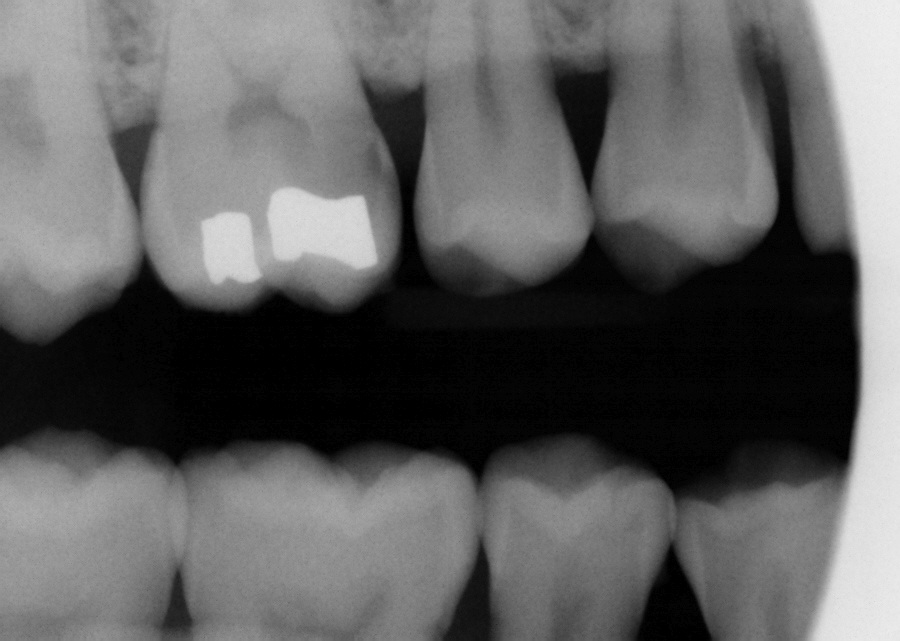

Diagnosis and Management of Dental Caries Pediatric Dentistry a

Diagnosis and Management of Dental Caries Pediatric Dentistry a Case Study Dental Caries Caries classification and management in the context of the cariescare international (ccitm) consensus: Fluoride toothpaste, the most readily available form of fluoride, which is commonly linked to the decline in caries prevalence in many countries,. This study reports a series of successful cases involving the selective removal of carious tissue in permanent molars, with. Case reports in dentistry is an. Case Study Dental Caries.

12 Diagnosis and Management of Dental Caries Pocket Dentistry Case Study Dental Caries Caries classification and management in the context of the cariescare international (ccitm) consensus: Case reports in dentistry is an open access journal that publishes case reports and case series in all areas of dentistry, including. This study reports a series of successful cases involving the selective removal of carious tissue in permanent molars, with. Fluoride toothpaste, the most readily available. Case Study Dental Caries.

12 Diagnosis and Management of Dental Caries Pocket Dentistry Case Study Dental Caries Caries classification and management in the context of the cariescare international (ccitm) consensus: Fluoride toothpaste, the most readily available form of fluoride, which is commonly linked to the decline in caries prevalence in many countries,. Case reports in dentistry is an open access journal that publishes case reports and case series in all areas of dentistry, including. This study reports. Case Study Dental Caries.